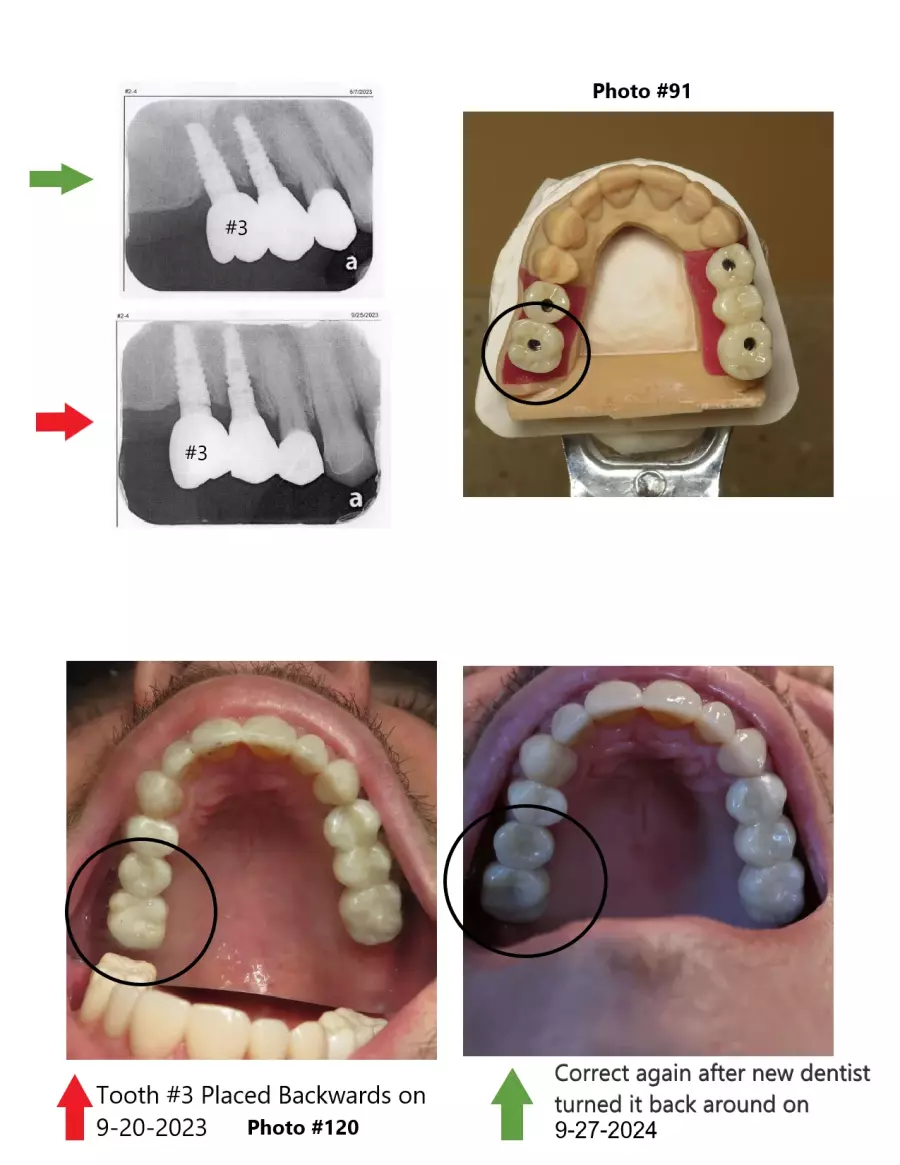

WMDDS please go look at photo #120 - This is a huge oversight error.

Dr. Rebecca Vanderbaan & Dr. Larissa Bishop The Past President Of The WMDDS Placed A Dental Crown Tooth #3 Backwards And Wrecked My Restoration. A Bridge became loose, A veneer chipped, A crown fell off, another crown became loose, 8 teeth are not touching each other and I have bone loss on several new implants likely caused from this.

How did a implant supported crown get placed 180 degrees backwards then get missed then several adjustments to the adjacent teeth were made on four different separate occasions until there was no bite on 8 teeth. Permanent adjustments were made to teeth #5, #6, #7, #26, #27 and #28 all based on a crown tooth number 3 being placed backwards and then let me go with a non-functioning bite.

The WMDDS should be looking hard at Photo #120 and look close at tooth #3 then compare it to the model the way the tooth was supposta be placed and you will see tooth #3 was placed 180 degrees backwards and not known for a whole year biting my tongue and cheek everyday over 300 times and sometimes to the point of bleeding and I told the dentist my tooth #3 is biting my tongue and check every single day but everyone ignored it and let me keep biting myself. Photo #120 is the photo that the dental association was weirdly missing. The WMDDS should go back and actually look at this case and see how the clinical exam was unfair, biased and no x-rays or bitechecks were even taken during there clinical exam.